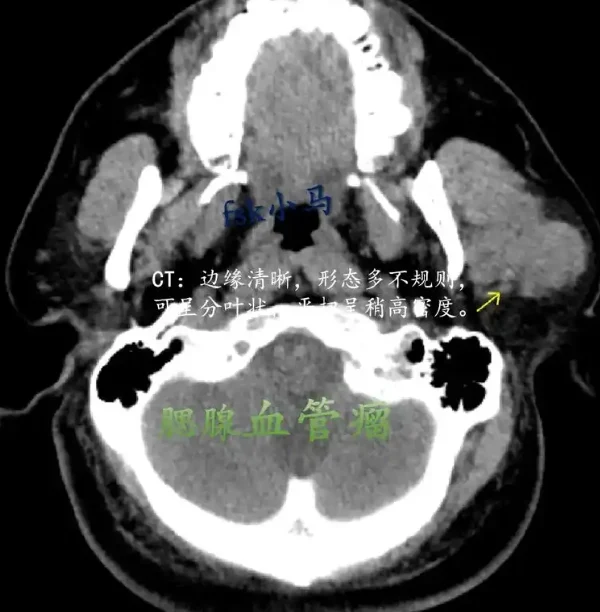

在这篇文章中,我们将探讨一个典型的病例。患者来自吉林省四平市,年龄50岁,身高176厘米,体重80公斤。检查显示,这名患者被诊断为腮腺瘤,但其具体的影像资料和详细数据暂未披露。临床上,他们接受了术前用药和各项麻醉剂量,准备进一步的手术治疗。

对于很多人来说,腮腺瘤可能是一个相对陌生的名词。腮腺瘤是一种发生在腮腺的良性肿瘤。通过本文,我们将为您详细解析腮腺瘤的潜在危害、治疗方法和预防措施。

腮腺瘤是腮腺细胞异常增生形成的肿瘤,通常是良性的。这种肿瘤最常见的症状是面部无痛性肿块。有时候,腮腺瘤也可能影响面神经,导致面部麻木或疼痛。虽然大多数腮腺瘤是良性的,但它们也有可能恶变为恶性肿瘤,因此需要及时诊断和治疗。